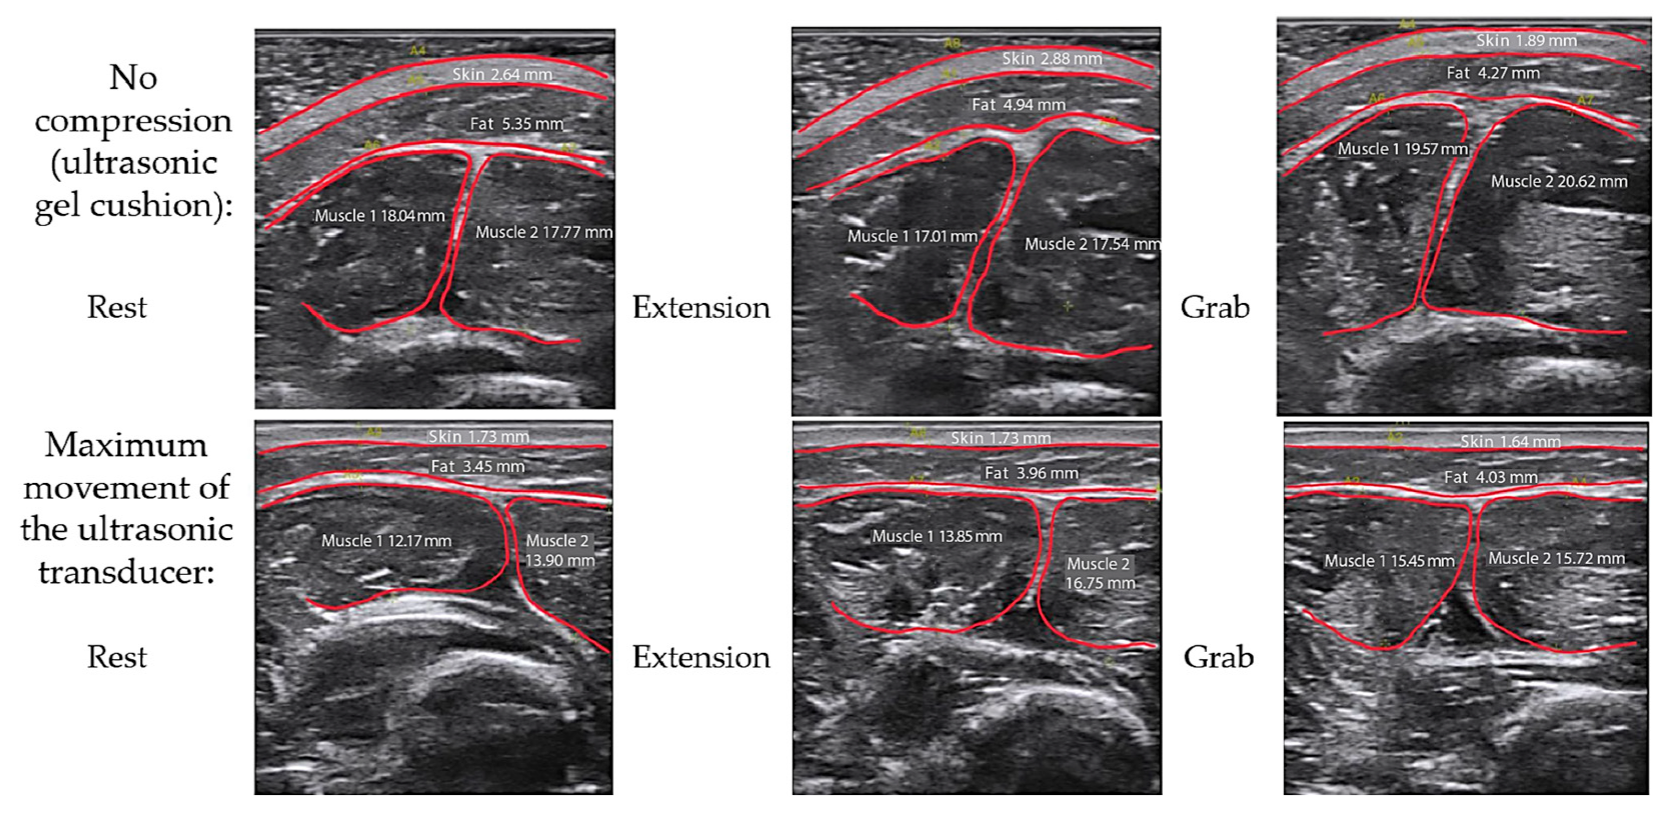

3.1. Study of Morphofunctional Activity of the Forearm Muscles When Performing Actions

3.2. Study of the Amplitude Parameters of the Electrical Impedance Myography Signal at Different Pressures of the Electrode System